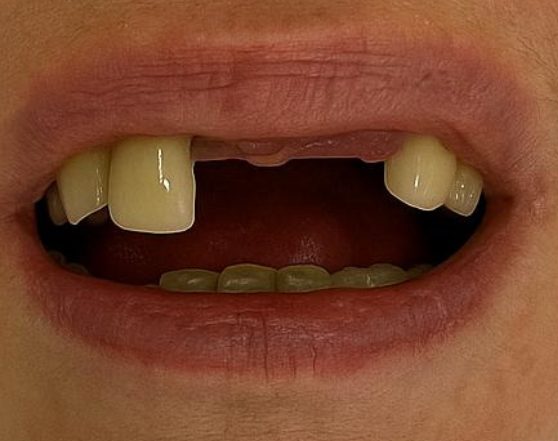

Two Front Implants

Upper right central and lateral incisors

Before

After